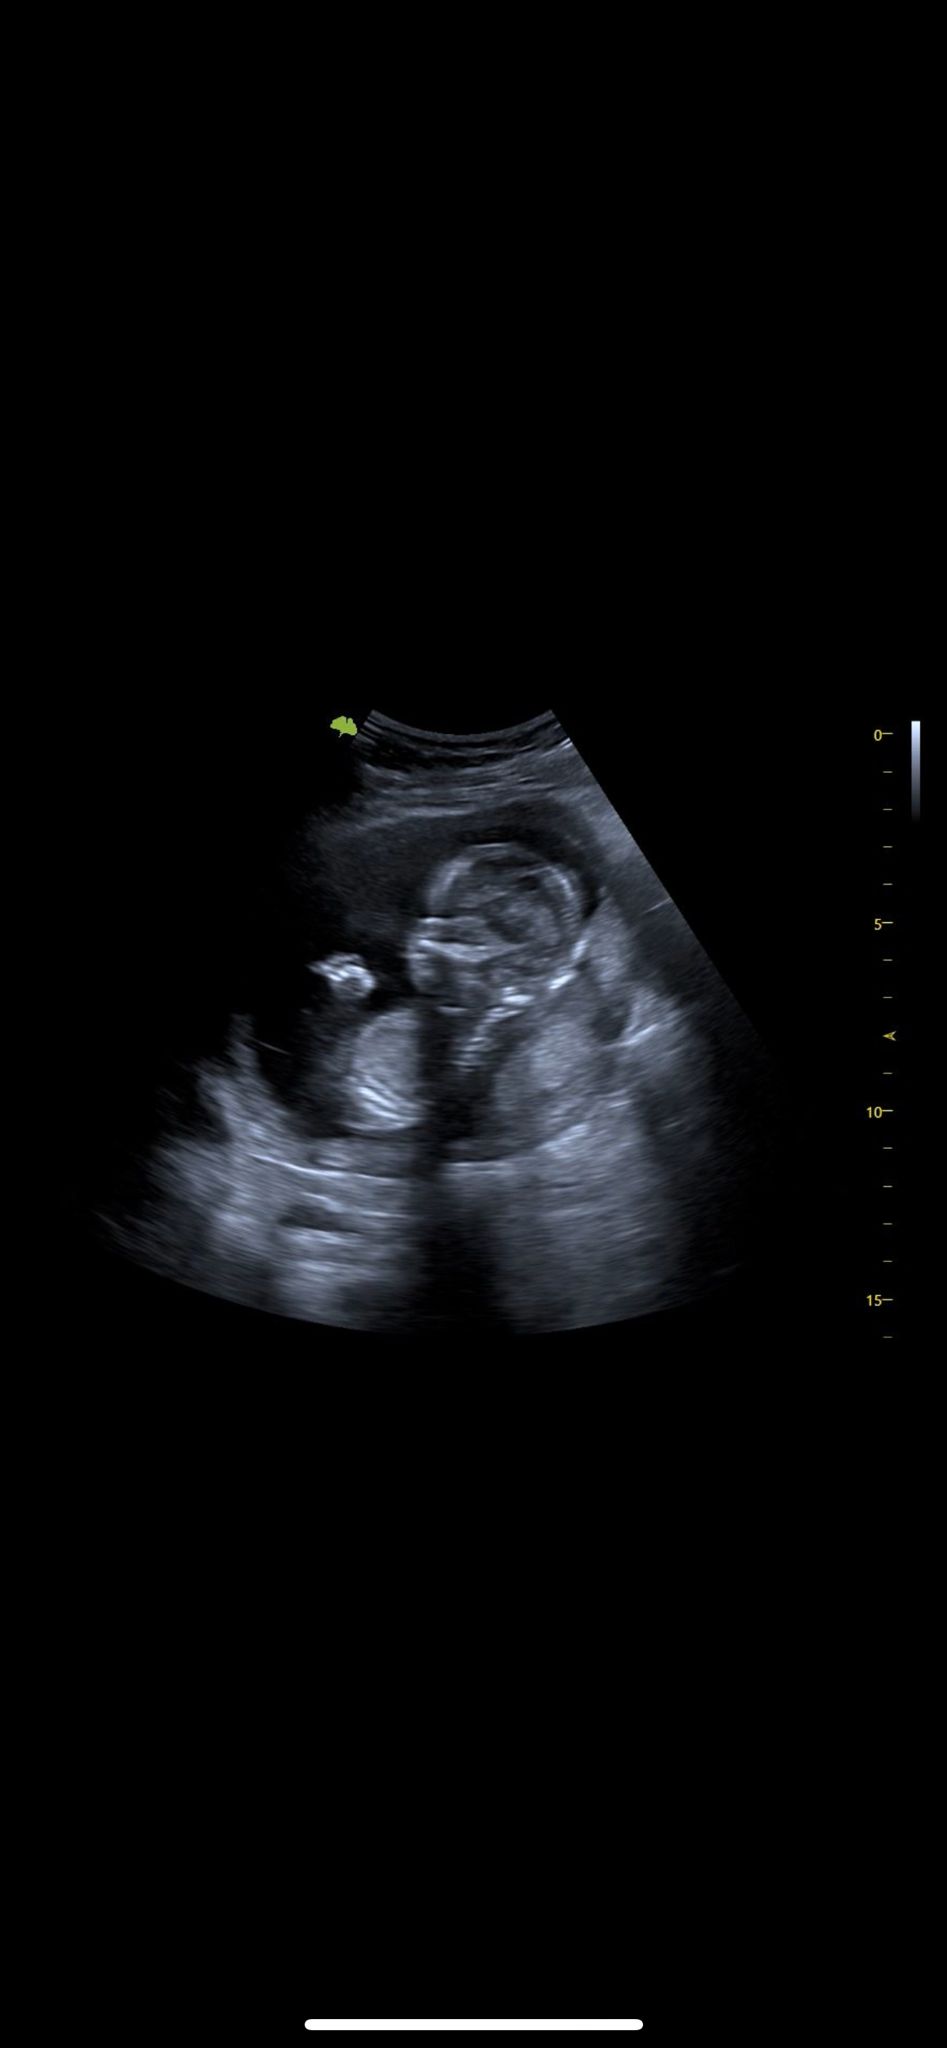

2D Echo

Op elk moment tijdens de zwangerschap mogelijk. Je ziet je kindje in zwart-wit bewegende beelden. Je kunt de handjes en voetjes zien en zelfs zien of het kindje duimt.